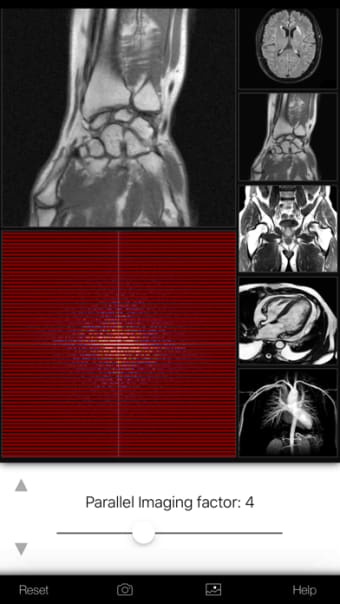

K-Space Odyssey strong>はiPhone用のフルバージョンのアプリで、カテゴリの一部になっています。医学'。

iPhone用K-Spaceオデッセイについて

K-Space Odysseyは、iOS12.1.2以降で利用できます。ソフトウェアの現在のバージョンは1.9.1であり、英語でのみ入手できます。 p>